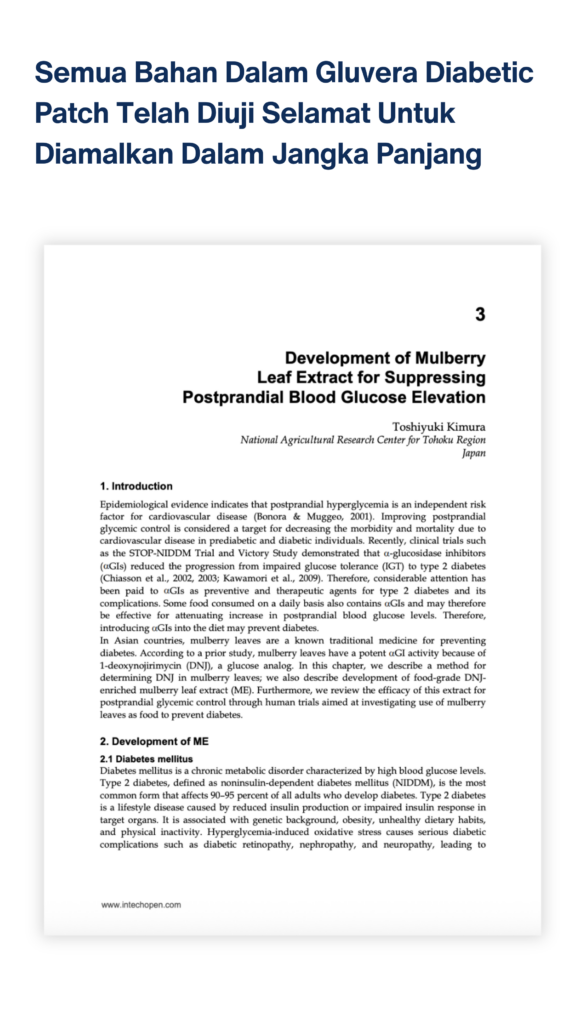

Disclaimer

*These statements have not been evaluated by the Food and Drug Administration. This Product is not intended to diagnose, treat, cure or prevent any disease. All finding or facts are based on scientific paper made into layman language so there many people out there realize the potential certain plant and biodiversity bring to their best of health.